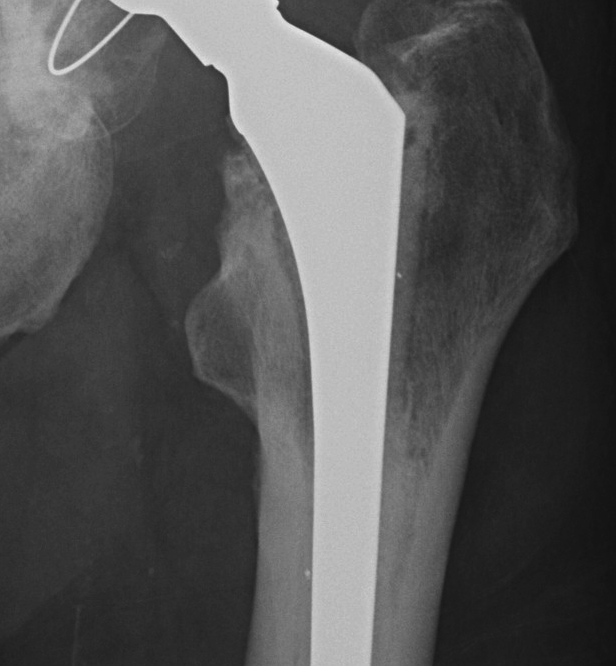

Cemented Femur

Signs of cemented femoral component loosening

O'Neil & Harris JBJS Am'84

3.  Definite

1.  Cement fracture

2.  Femoral stem fracture

3.  New lucency cement - implant interface

4.  Stem migration

THR Probably LooseTHR Exeter Stem Fracture

A.  Subsidence

- 1-2 mm normal in first year

- > 5 mm abnormal

- measure from tip GT to head neck junction

B.  Medial midstem pivot

- pivots about midstem

- proximal medial, distal lateral

- poor cement superomedial or inferolateral

C.  Calcar pivot / bending cantilever

- distal fix strong, but proximally loose

- breakdown of proximal cement

- bone destruction